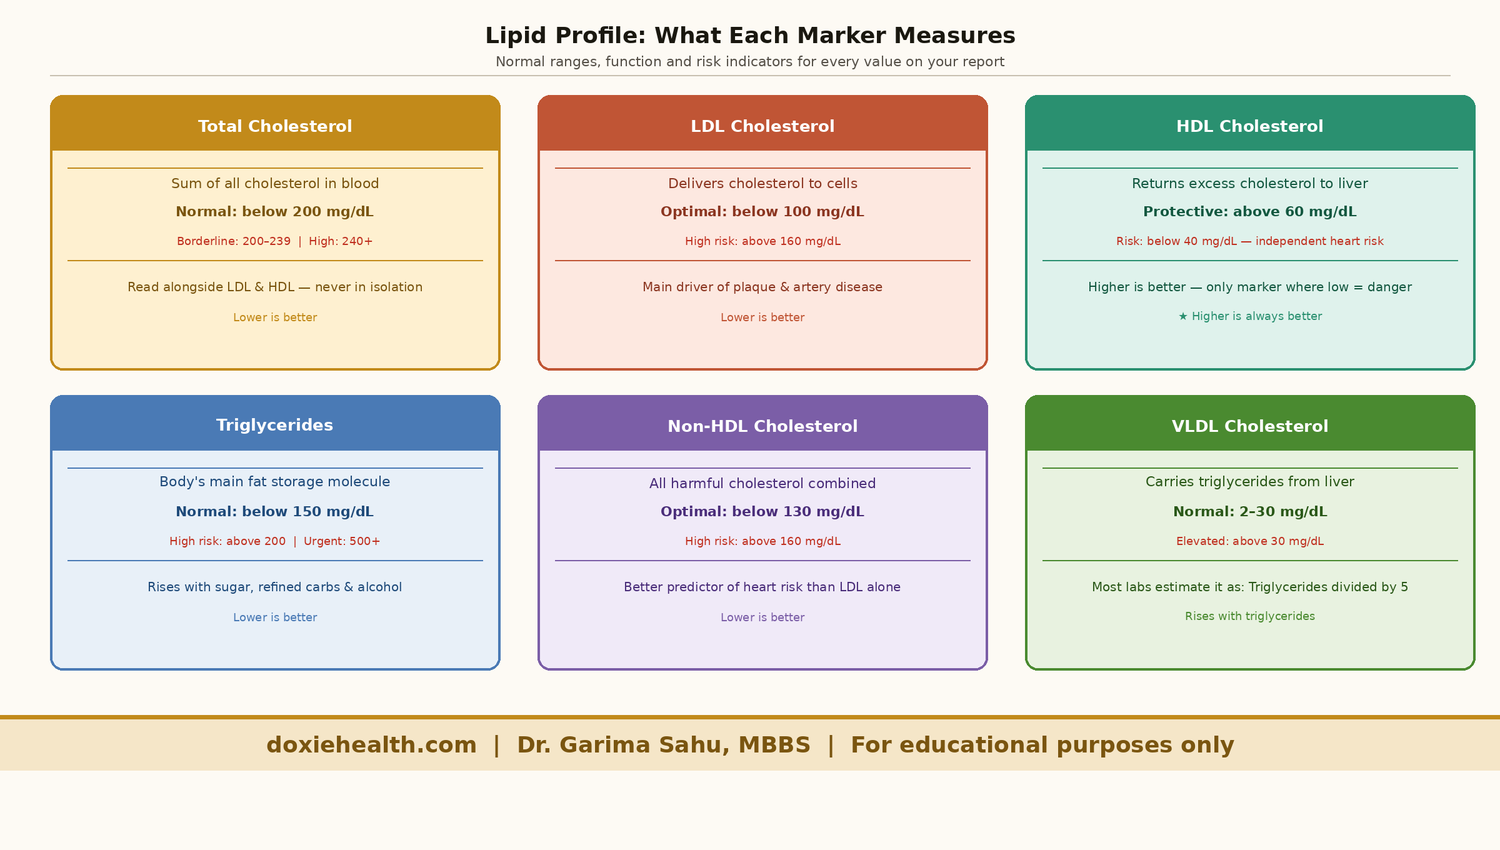

Quick Reference: Normal Lipid Profile Ranges

Standard adult reference ranges. Your lab report may show slightly different values.

| Marker | Optimal | Borderline | High Risk |

| Total Cholesterol | Below 200 mg/dL | 200–239 mg/dL | 240+ mg/dL |

| LDL Cholesterol | Below 100 mg/dL | 130–159 mg/dL | 160+ mg/dL |

| HDL Cholesterol | Above 60 mg/dL ✓ | 40–59 mg/dL | Below 40 mg/dL |

| Triglycerides | Below 150 mg/dL | 150–199 mg/dL | 200+ mg/dL |

| Non-HDL Cholesterol | Below 130 mg/dL | 130–159 mg/dL | 160+ mg/dL |

| VLDL Cholesterol | 2–30 mg/dL | — | Above 30 mg/dL |

| TC/HDL Ratio | Below 3.5 | 3.5–5.0 | Above 5.0 |

| LDL/HDL Ratio | Below 2.5 | 2.5–3.5 | Above 3.5 |

For HDL — higher is better. It is the only marker where a low value is the concern.

Lipid Profile Markers

Total Cholesterol

It is the first number most people look at, but also the most misleading when read in isolation.

This does not represent all the cholesterol in your body. Instead, it reflects the amount of cholesterol present in your bloodstream at that moment.

Total cholesterol is the sum of all cholesterol types in your blood carried by different lipoproteins:

| Total Cholesterol ≈ LDL + HDL + VLDL |

Why Total Cholesterol Alone Is Not Enough

Total cholesterol doesn’t tell the full story. Two people can have the same value but very different risk levels depending on their LDL and HDL.

- High LDL + low HDL → higher risk

- Low LDL + high HDL → lower risk

For example, a total cholesterol of 220 mg/dL could mean either unhealthy LDL levels or simply high HDL. That’s why the breakdown matters more than the total cholesterol alone. This is why total cholesterol is always read alongside the breakdown.

LDL Cholesterol — Direct

LDL (Low-Density Lipoprotein) is the primary carrier of cholesterol from the liver to the rest of the body.

When LDL levels are too high, excess cholesterol is deposited into artery walls, forming plaques — a process called atherosclerosis. It is the single most important number on your lipid profile.

HDL Cholesterol — Direct

HDL (High-Density Lipoprotein) works in the opposite direction to LDL. It collects excess cholesterol from artery walls and transports it back to the liver for removal — a process called reverse cholesterol transport.

HDL is the only marker on your lipid profile where higher is better.

Triglycerides

Triglycerides are your body’s main fat storage molecule — think of them as a fuel reserve. When you consume more calories than you burn, particularly from sugar and refined carbohydrates, the excess is converted into triglycerides and stored in fat cells for later use.

Non-HDL Cholesterol

Non-HDL cholesterol is calculated as Total Cholesterol minus HDL. It captures all cholesterol carried by potentially harmful particles — LDL, VLDL, and IDL — in a single number.

Many cardiologists consider non-HDL cholesterol a better predictor of cardiovascular risk than LDL alone, because it accounts for all plaque-forming particles, not just LDL.

The target for most adults is below 130 mg/dL — 30 points higher than the LDL target.

VLDL Cholesterol

VLDL (Very Low-Density Lipoprotein) is the liver’s primary transporter of triglycerides into the bloodstream.

It is closely linked to triglyceride levels — when triglycerides rise, VLDL typically rises with them. Normal range is 2–30 mg/dL.

VLDL contributes to plaque formation, though it is considered less harmful than LDL.